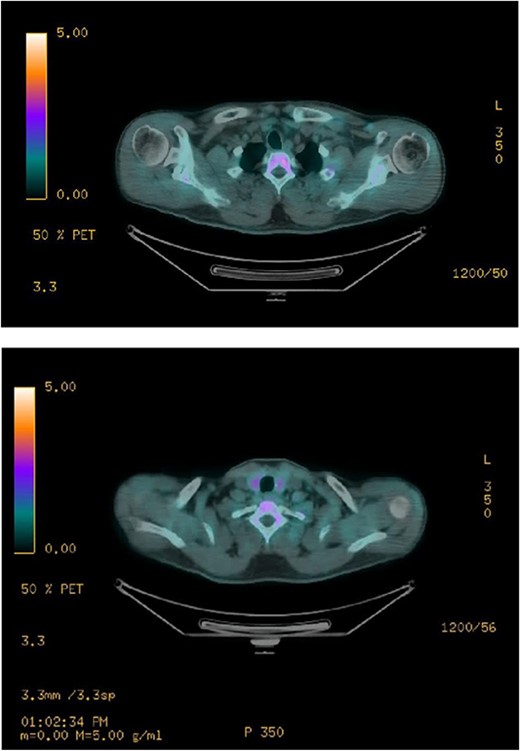

Ultrasound of the neck (Fig. 1), CT and parathyroid sestamibi scan (Fig. 2) failed to localize parathyroid, and all studies showed normal thyroid with no other neck masses or suspicious lymph nodes. Magnetic resonance imaging neck showed no evidence of parathyroid adenoma in the expected typical gland locations or ectopic cervical or upper mediastinum. Therefore, we requested a fluorocholine (FCH) positron emission tomography (PET)/CT (Figs 3 and 4) for localization, which showed normal physiological uptake of the choline in the neck. There was no abnormal focal choline lesion in the thyroid gland or the visualized organs (unremarkable visualized part of the lungs). So, the result was a negative choline scan.

Ultrasound neck showing normal thyroid gland and no abnormal parathyroid.